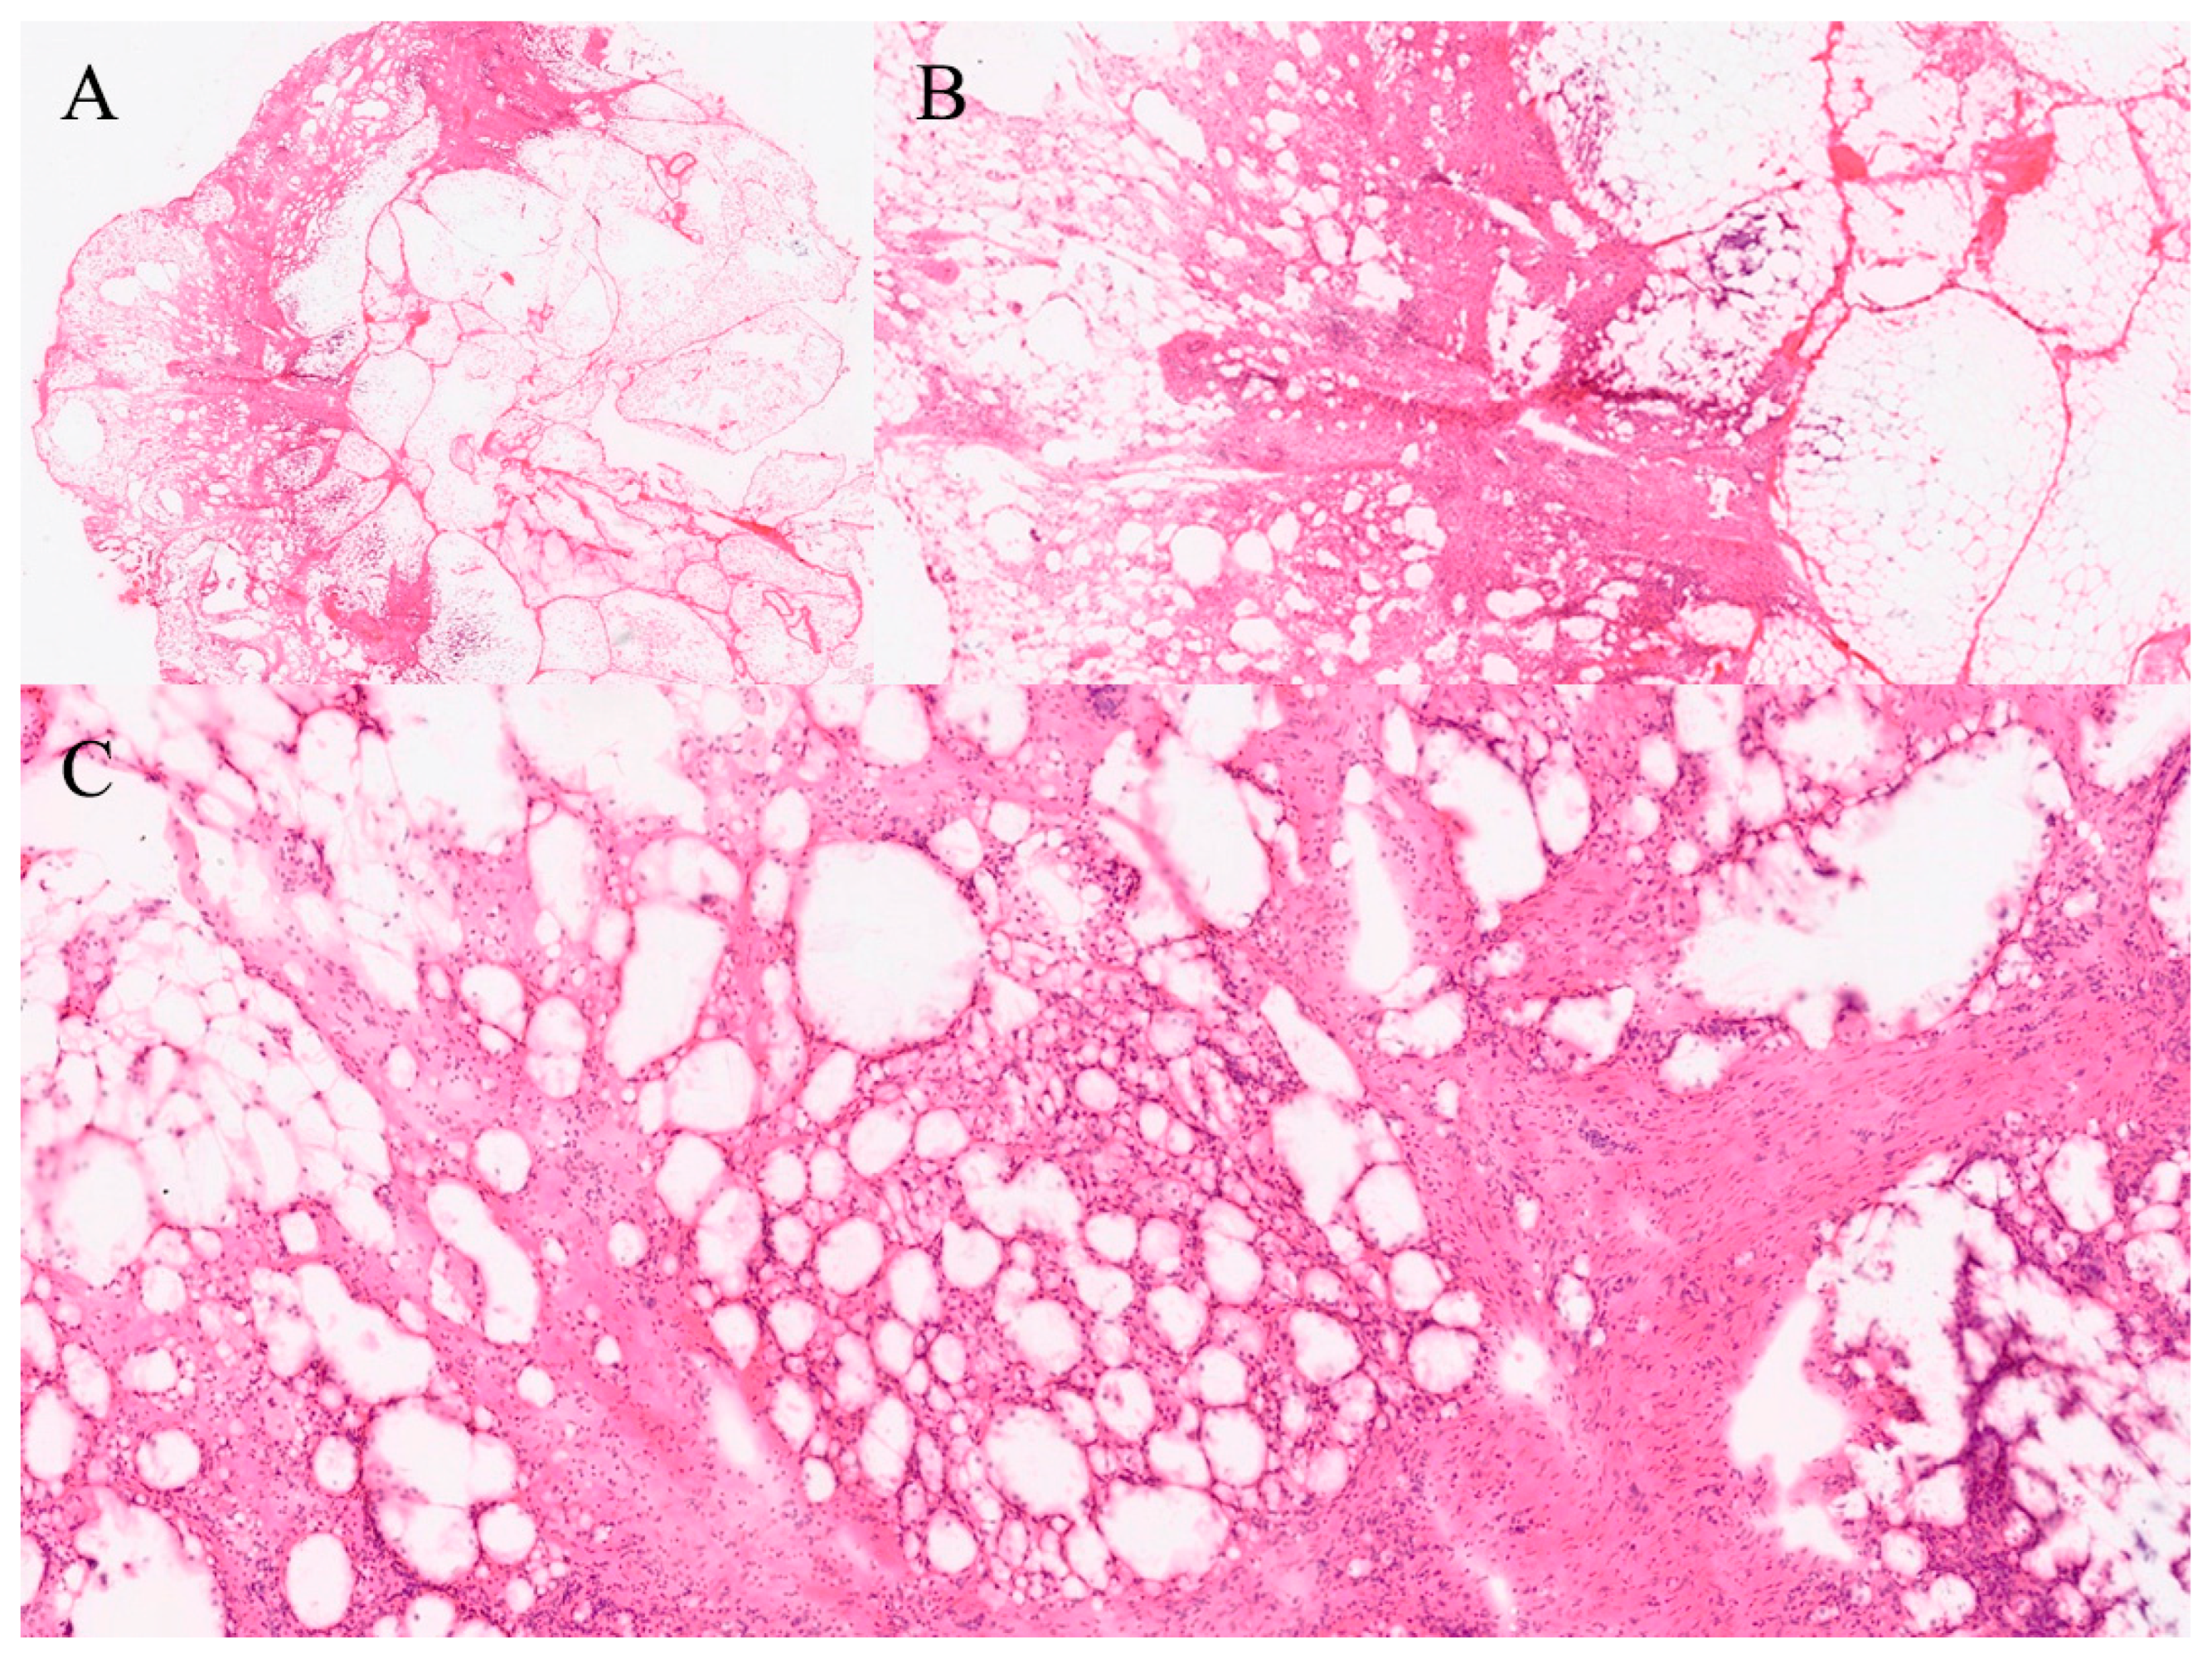

4.7. Cystic Lesions of the Liver or Pancreas

Cystic lesions are evaluated to detect mucinous neoplasms and assess for malignancy [39]. In the pancreas, differentiating mucinous cysts—such as MCNs and IPMNs—from non-mucinous lesions is critical given their higher malignant potential [40]. FS findings influence operative choice and prognosis, especially when invasive carcinoma is detected [41].